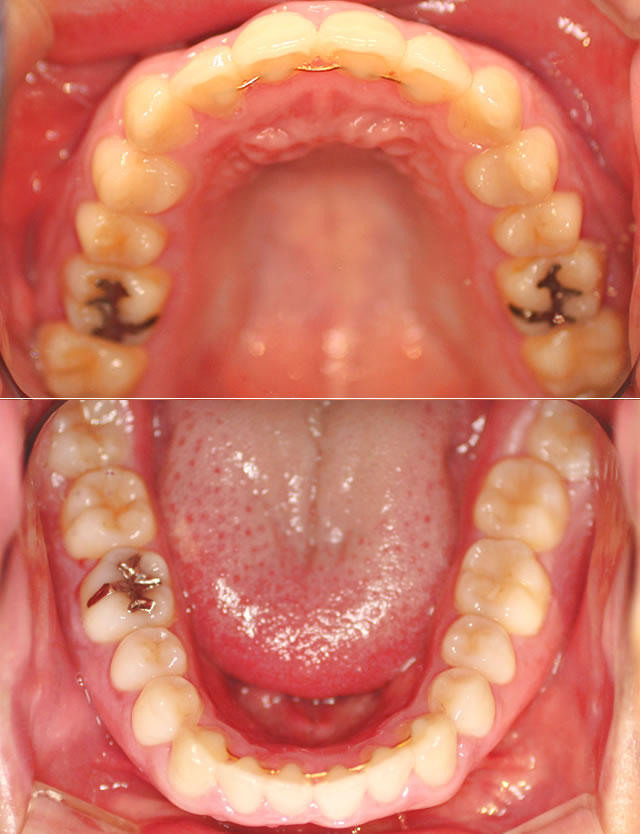

治療前・咬合面

治療後・咬合面